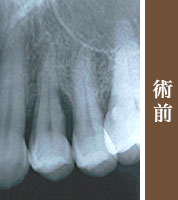

歯周病が進行して支えている骨は少ない、このままでは最終的には抜歯です(レントゲンでは歯の周りの骨の無くなった状態は黒く、骨は白くもやもやした像に写ります)。